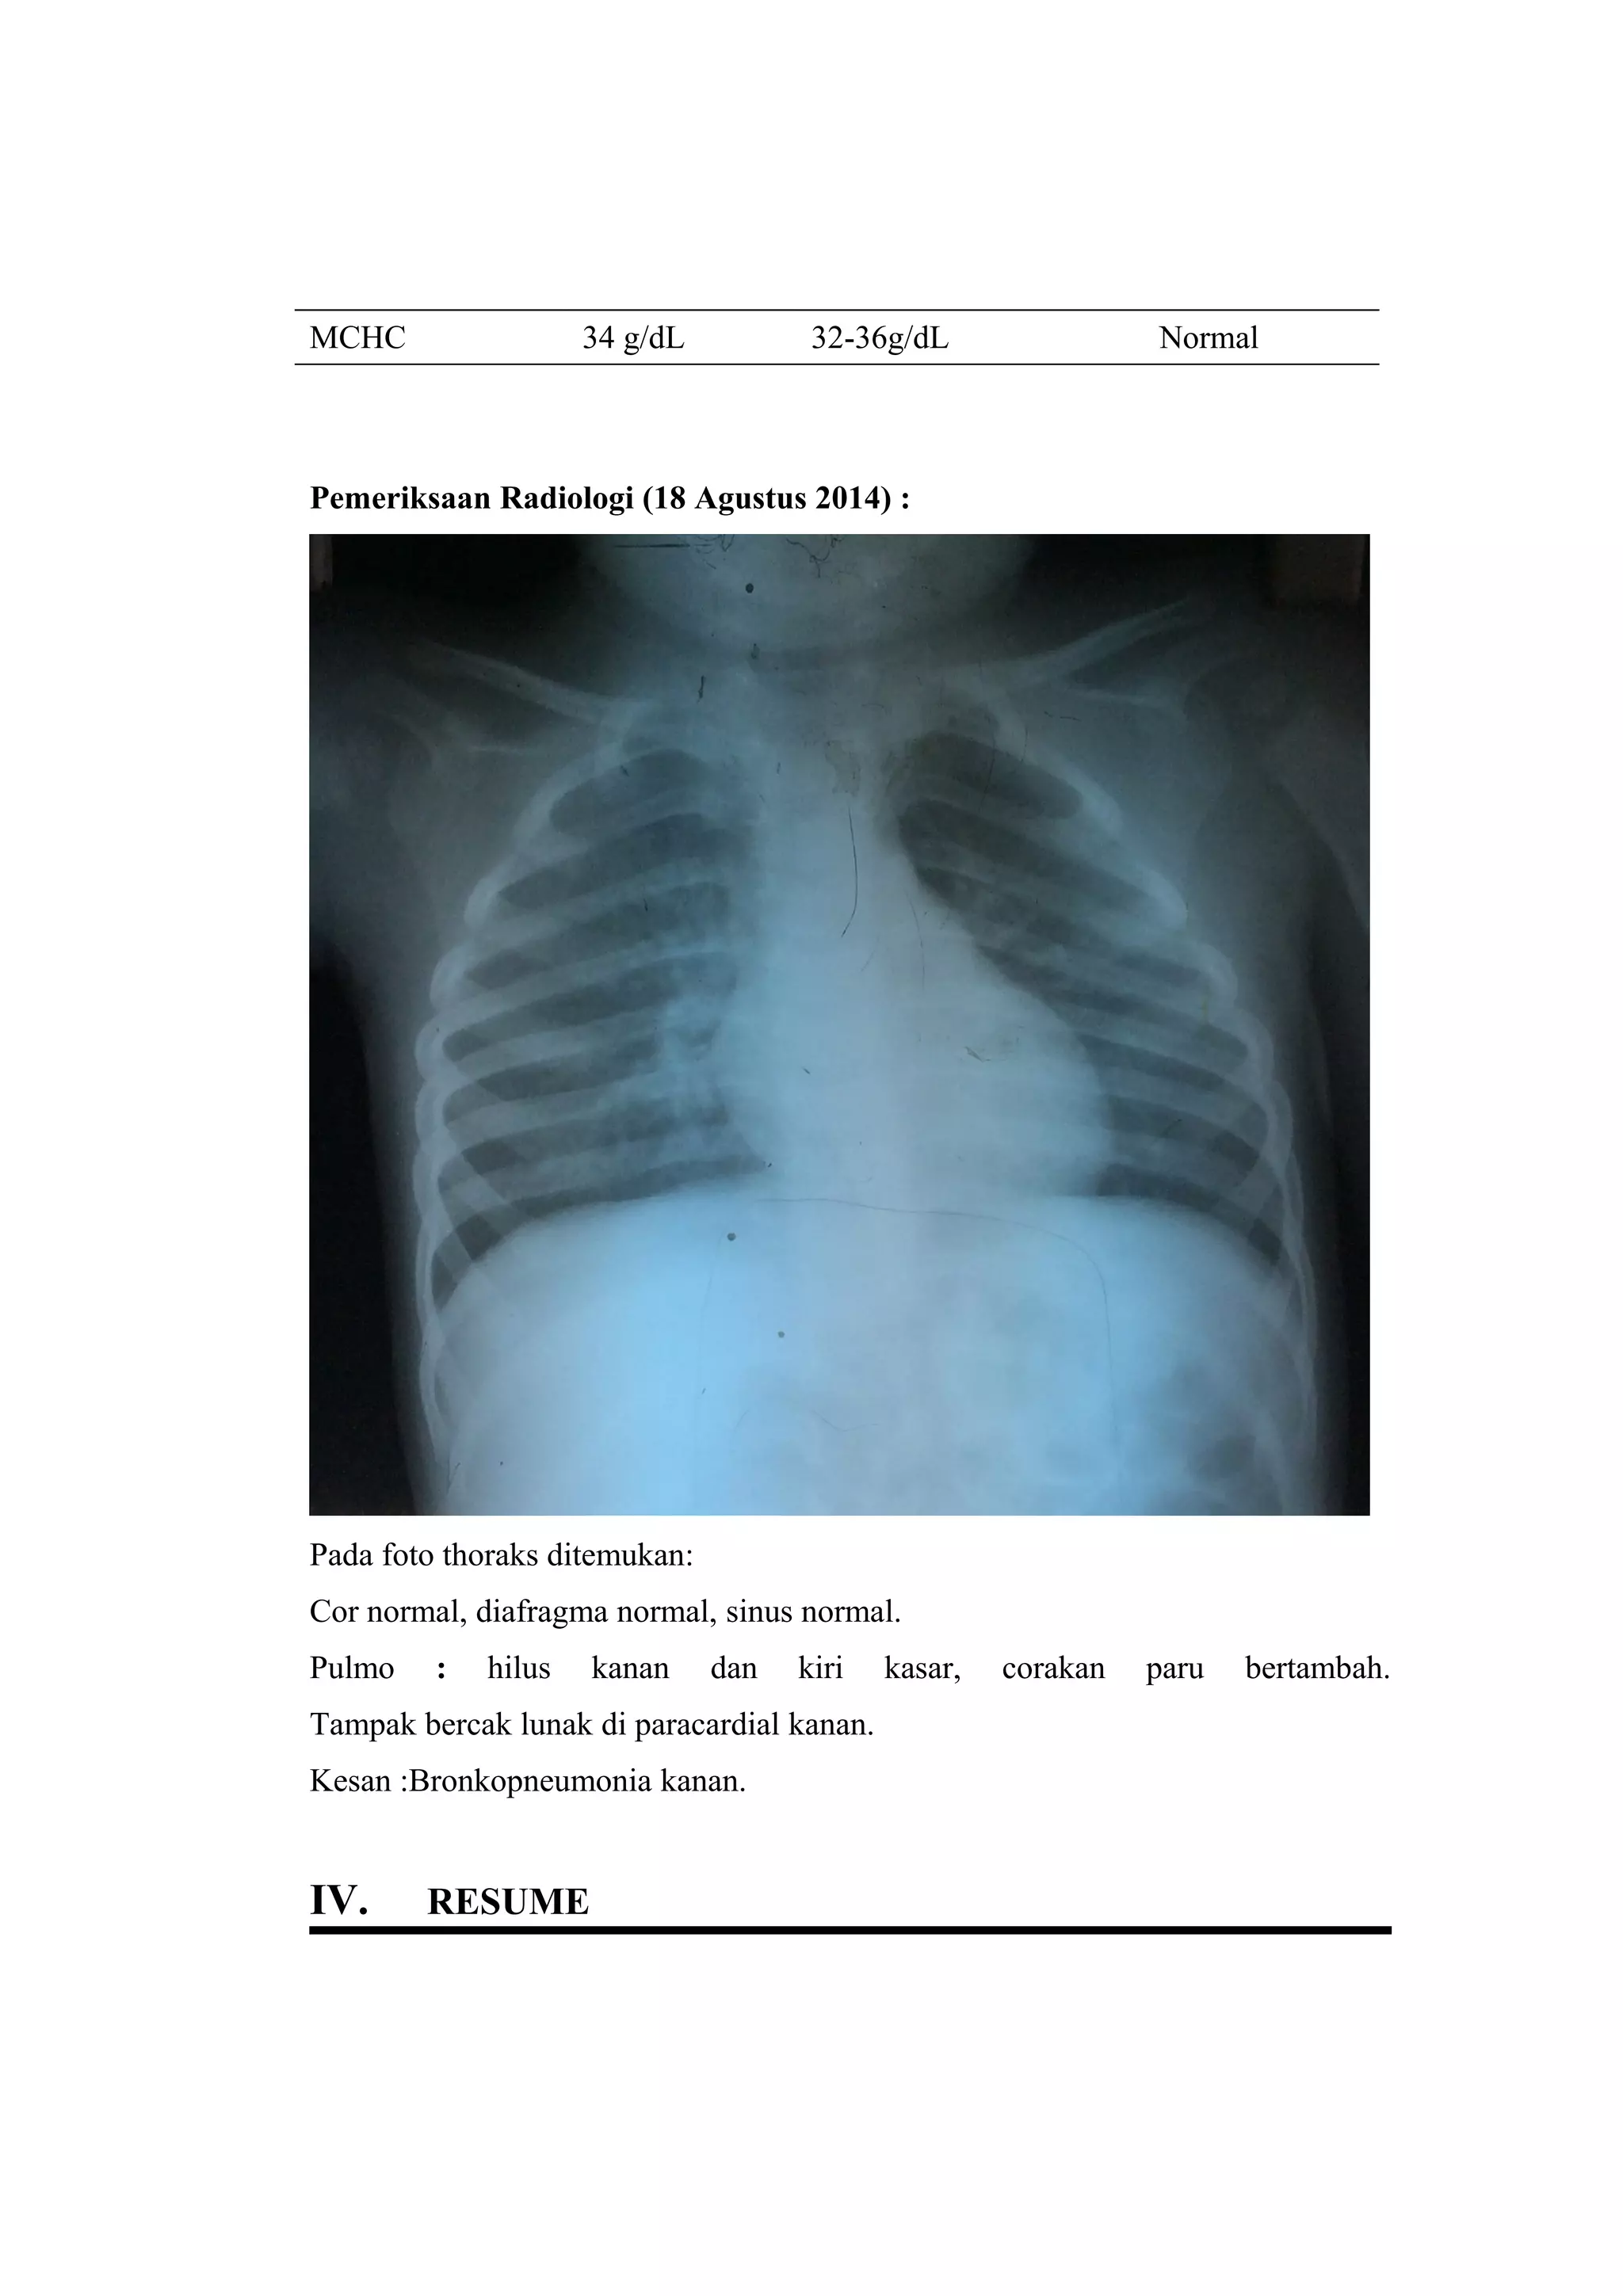

Pemeriksaan Radiologi (18 Agustus 2014) :

Pada foto thoraks ditemukan:

Cor normal, diafragma normal, sinus normal.

Pulmo : hilus kanan dan kiri kasar, corakan paru bertambah.

Tampak bercak lunak di paracardial kanan.

Kesan :Bronkopneumonia kanan.